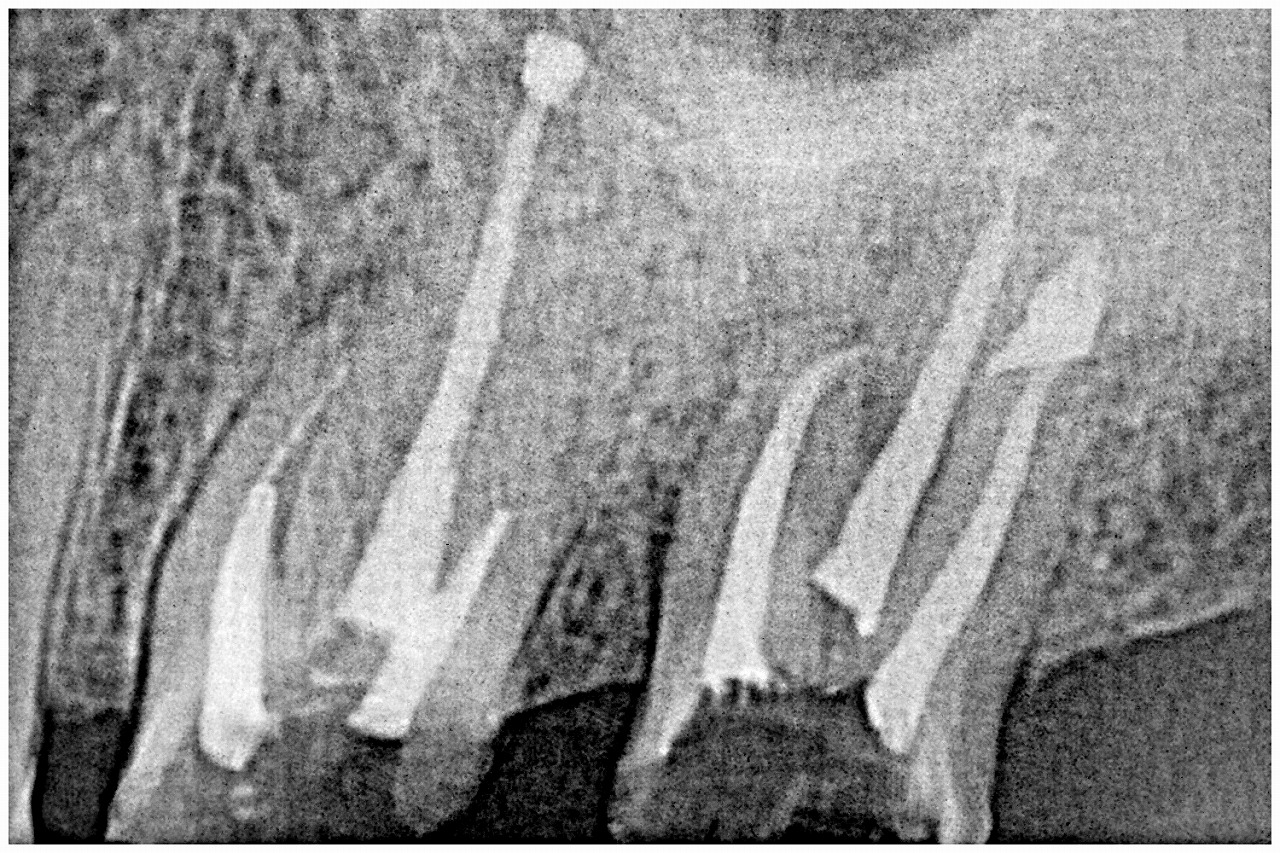

デンタルレントゲンになります

分岐部に至るまで大きく骨吸収が存在

破折が疑われます

根管治療から行っていきました